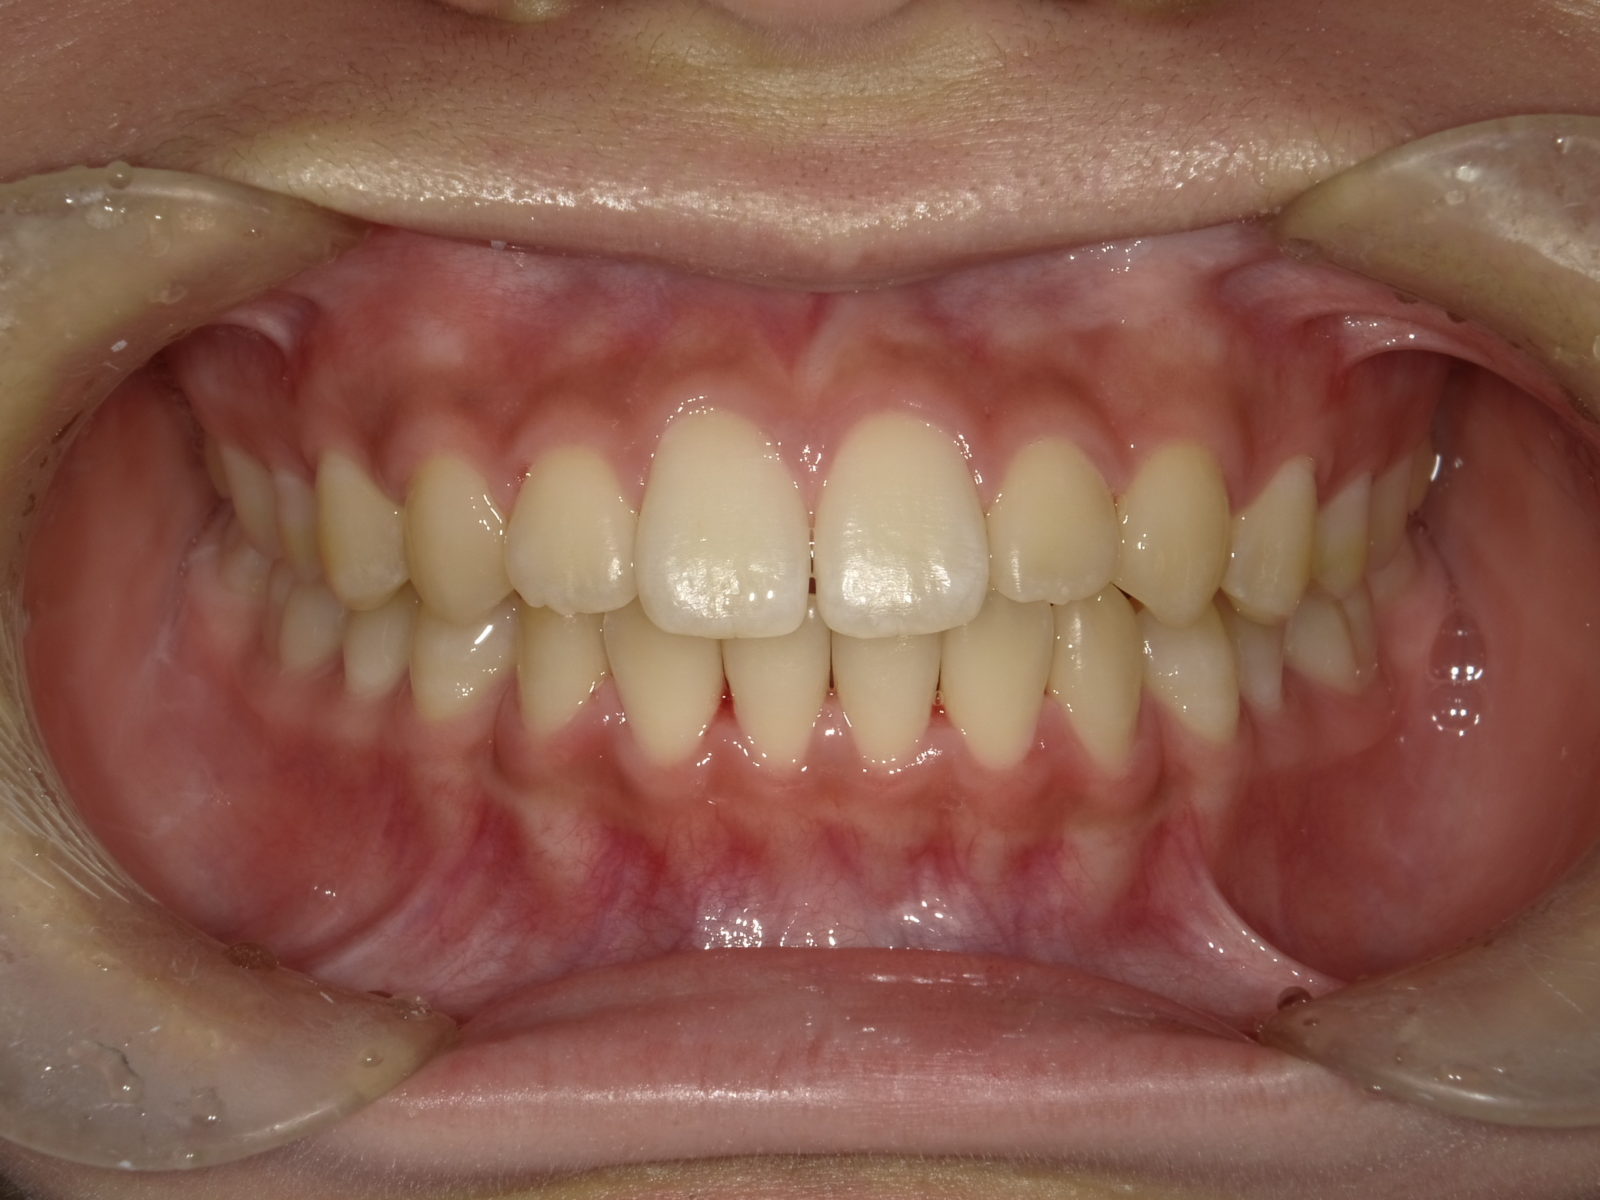

顎顔面矯正は、「急速拡大装置」を利用し、正中口蓋縫合と呼ばれる部分を広げ、顎骨の成長を促していきます。下の画像のように「ねじ」を回すことで装置を徐々に広げていきます。